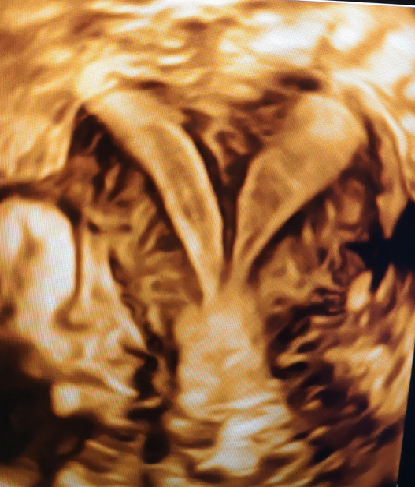

盆底超聲動態(tài)下檢查產(chǎn)后盆底功能